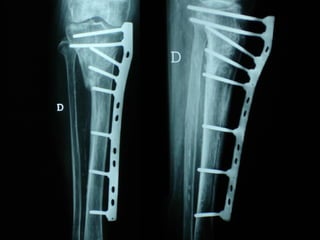

Dal Gennaio 2000 al Febbraio 2006 abbiamo trattato 167 fratture chiuse  con placca percutanea  in 164 pazienti :  27 lesioni diafisarie di gamba, 12 piloni tibiali ,  11 fratture prossimali di tibia, 36 fratture sovracondiloidee di femore, 17 fratture diafisarie di femore, 43 fratture metaepifisarie prossimali di omero, 21 diafisarie d’omero.  156 guarigioni 8 fallimenti

I buoni risultati ottenuti dipendono da 5 punti fondamentali:   una accurata riduzione percutanea della frattura  precise vie di accesso  l’utilizzo della placca che consenta il più lungo braccio di leva possibile il pretensionamento della placca  una sintesi con un ridotto numero di viti

Precise vie di accesso

Placche lunghe e pretensionate

Placche lunghe e pretensionate Sintesi con un ridotto numero di viti